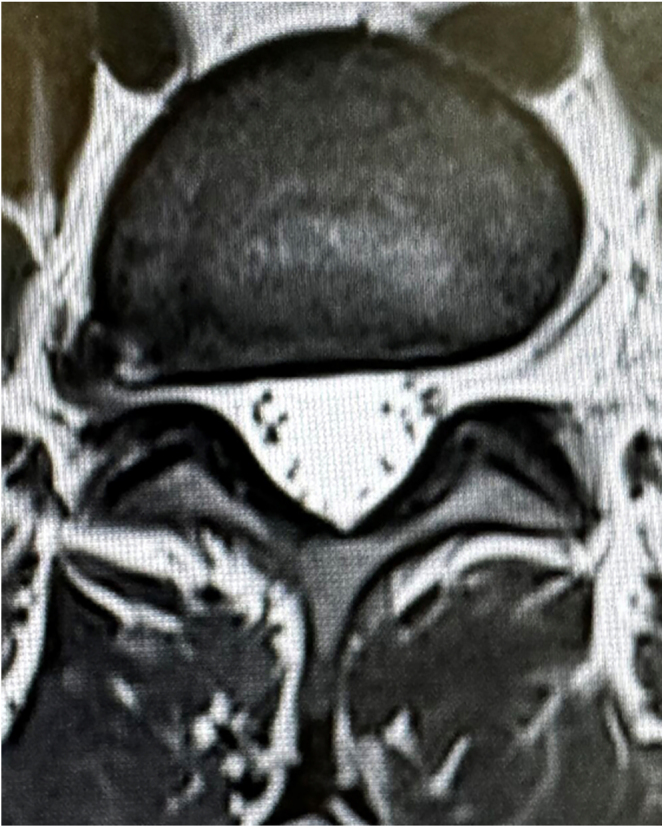

Foraminal and extraforaminal lumbar disc herniations are common sources of pain and disability. Classic surgical treatments, such as open approach through Witsel technique, often involve resection of the superior articular process to decompress the foraminal space. Unilateral biportal endoscopy (UBE) has emerged as a minimally invasive alternative, providing enhanced visualization and precision while minimizing soft tissue damage. The extraforaminal approach using UBE offers a more effective solution for extraforaminal herniations, requiring less bone resection, reducing the risk of pars fracture and enhancing visualization. This article presents a comprehensive methodology for the extraforaminal approach, supported by an illustrated guide, surgical tips and highlights of UBE's advantages over traditional techniques.